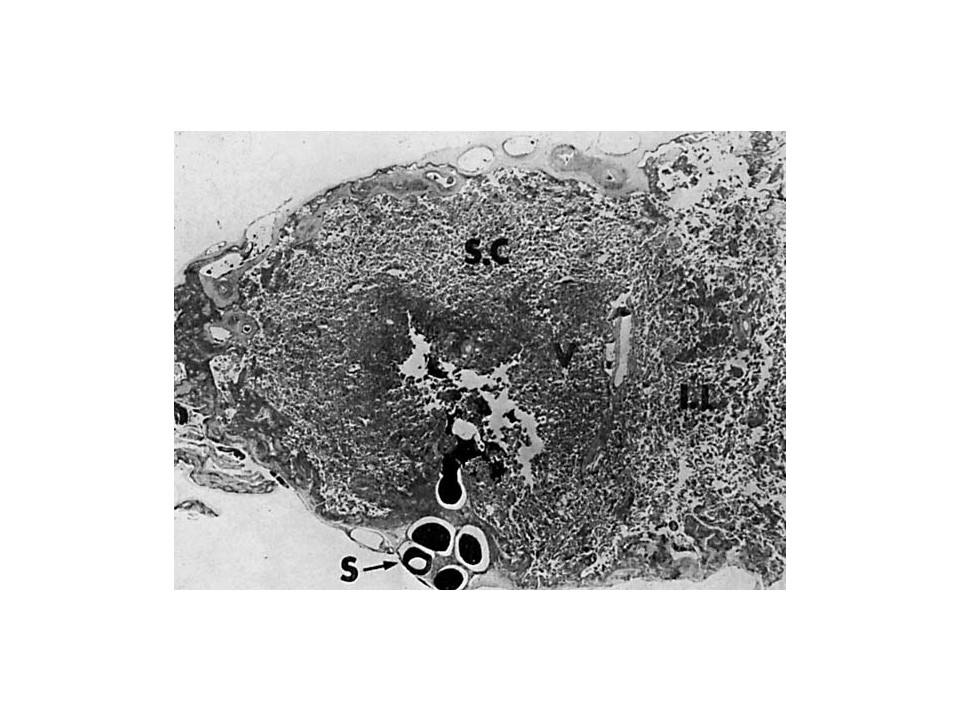

Vascular Anatomy of the Human Placenta